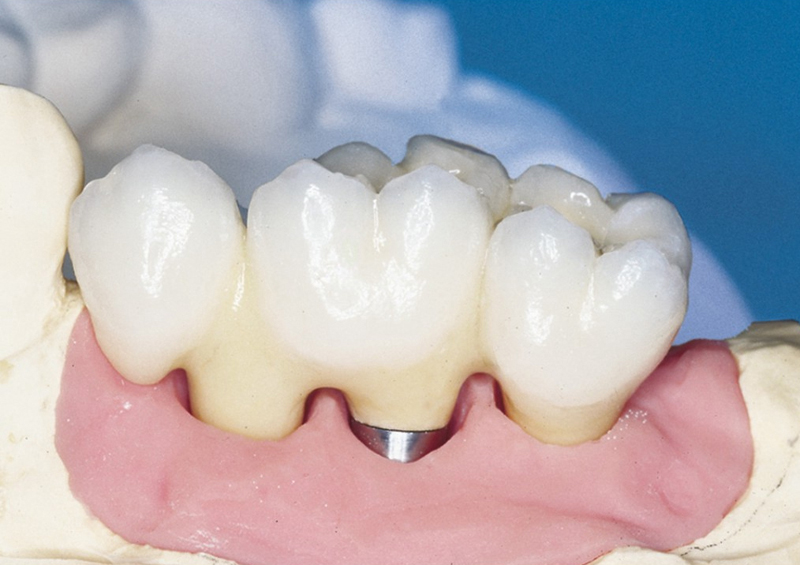

Pevné můstky – lepené nebo šroubované

Protetické řešení může být pomocí můstku, který je kotvený na implantátech nebo pomocí jednotlivých korunek na implantátech.

V zásadě je možné do těchto můstků zařadit i přirozené zuby, zejména pokud je potřeba tyto zuby ošetřit proteticky - korunkami. Korunky nebo můstky mohou být na implantáty nacementovány nebo přišroubovány.